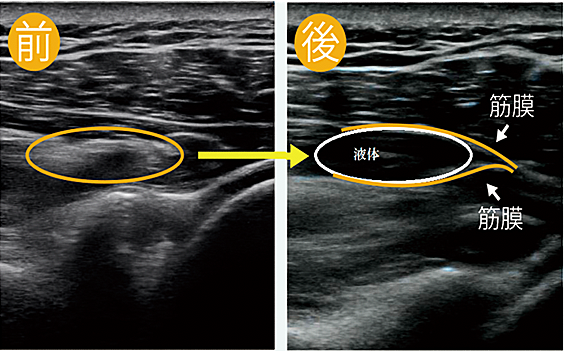

筋膜リリース/ハイドロリリース(先進医療)

肩こりや腰痛の筋肉と筋膜の癒着を剥がす先進医療です。生理食塩水や低濃度の麻酔剤を超音波ガイド下に正確に針を刺入し注入します。当院では先進医療の体外衝撃波と組み合わせダブル先進医療をやっております。

針が筋肉間に見える

薬液が筋膜下に注入